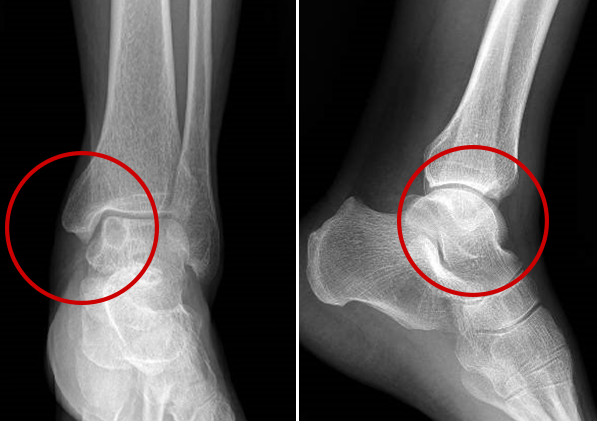

术前X线